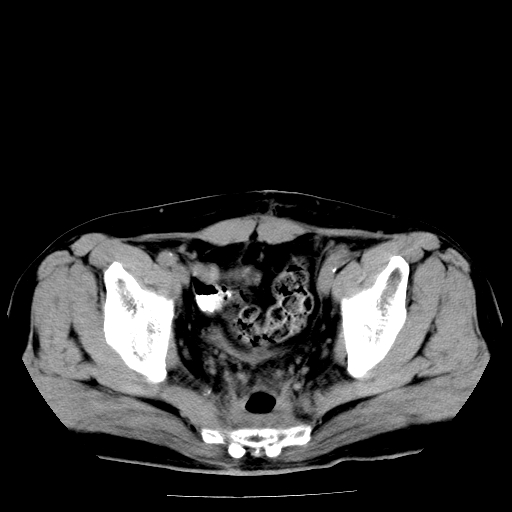

男,66岁,直肠癌术后一个月,化疗前ct检查。

直肠癌造瘘术后改变,周围淋巴结转移

前列腺肥大

直肠癌造瘘术后改变,盆腔多发淋巴结转移

直肠癌造瘘术后改变,直肠周围软组织增厚,盆腔多发淋巴结转移。前列腺肥大。